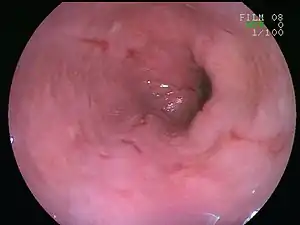

| An esophageal ulcer visualized by esophagoscopy: the reddened area at 10 o'clock on the surface of the mucosa. | |

If the disease remains untreated, it can cause scarring and discomfort in the esophagus. If the irritation is not allowed to heal, esophagitis can result in esophageal ulcers. Esophagitis can develop into Barrett's esophagus and can increase the risk of esophageal cancer.[3]

Esophagitis can be diagnosed by upper endoscopy, biopsy, upper GI series (or barium swallow), and laboratory tests.[4]

An upper endoscopy is a procedure to look at the esophagus by using an endoscope. While looking at the esophagus, the doctor is able to take a small biopsy. The biopsy can be used to confirm inflammation of the esophagus.